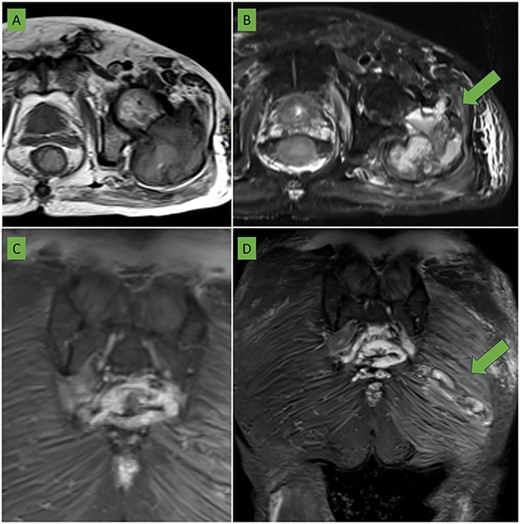

Bone scintigraphy of the entire skeleton, SPECT–CT of the pelvis (Fig. 2) and magnetic resonance imaging (MRI) was performed for surgical planning (Fig. 3A–C).

(A) T2 sequence with fat saturation and (B) T1-weighted sequence in axial plane centered on the left hip: a large expansive lesion is visualized centered in the trochanteric region extending to the femoral neck with a heterogeneous matrix of hyperintense predominance with respect to the muscle in both sequences in which cavities with liquid/liquid levels are identified (arrow) compatible with bleeding in different phases. The anterior cortex is focally rotated extending to the medial gluteal musculature (arrow). (C) Coronal section in STIR sequence showing sacrococcygeal involvement of the same characteristics as the femoral lesion. (D) Coronal section in STIR sequence centered in the gluteal region: an elongated lesion with lobulated borders is seen extending from the lateral region of the gluteus maximus to the proximity of the sacrococcygeal region (arrow). It coincides with the biopsy trajectory and is suggestive of tumor seeding.

In addition to previous lesion, an intramuscular soft tissue mass located in the left gluteus maximus not detected in the CT scan prior to the percutaneous biopsy, shows a probable tumor seeding in the trajectory towards the sacral region (Fig. 3D).